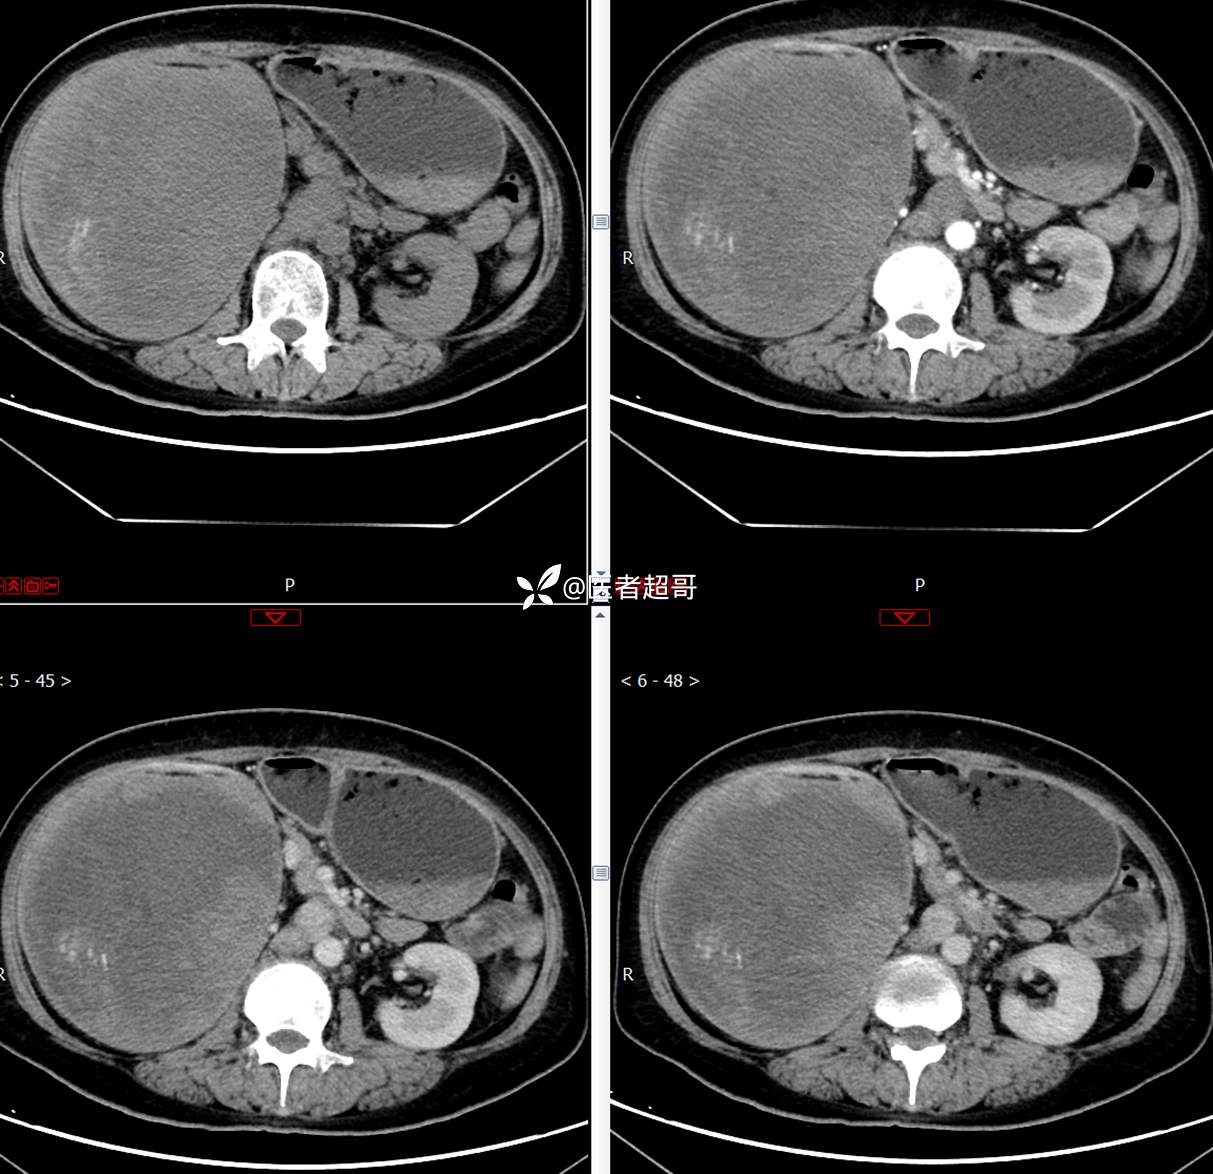

现病史:患者1周余前发现右上腹有一半球形巨大肿物,约18cm*15cm大小,既往贫血病史3年余,诉乏力,易疲劳,偶有头晕,活动后心悸,无腹痛、腹胀,无恶心、呕吐,无尿频、尿急、尿痛,无排尿困难,患者为求进一步治疗,来我院消化内科就诊,门诊行肝.胆.胰.脾.肾彩超示:右肾上部囊实性占位,范围约18.0cm×11.7cm×16.4cm,边界清,形态规则,建议进一步检查,腹膜后实性结节。我科遂以“肾肿物”收治入院,患者自发病以来,神志清、精神可,睡眠、饮食可,二便正常,体重、体力略有下降。